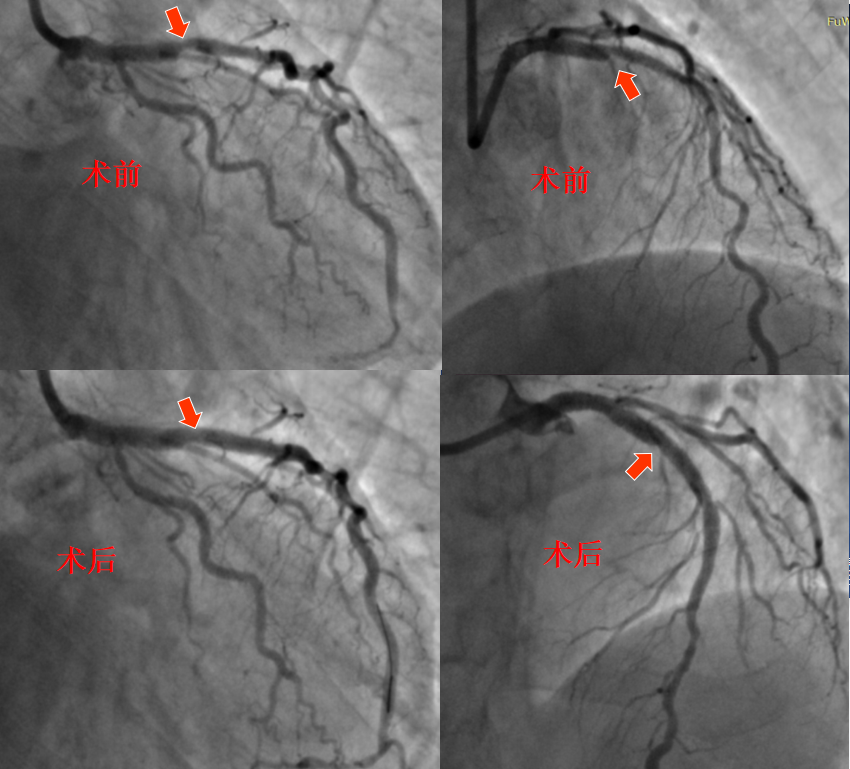

72岁的杨大爷是一位多年冠心病患者,18年前因患急性心肌梗死于当地医院行介入治疗植入支架。 2个月前又出现严重的胸闷、胸痛症状,转至我院冠心病二病区,经检查诊断为急性非ST段抬高型心梗。2022-06-29为患者进行冠脉造影复查,结果显示:左主干及多支血管病变合并严重钙化,其中前降支原支架内80-90%再狭窄;右冠状动脉95%狭窄,先对右冠状动脉病变行支架植入治疗,因患者病情复杂,计划1月后再次治疗左冠状动脉严重病变。

图1 6月29日介入治疗术中造影